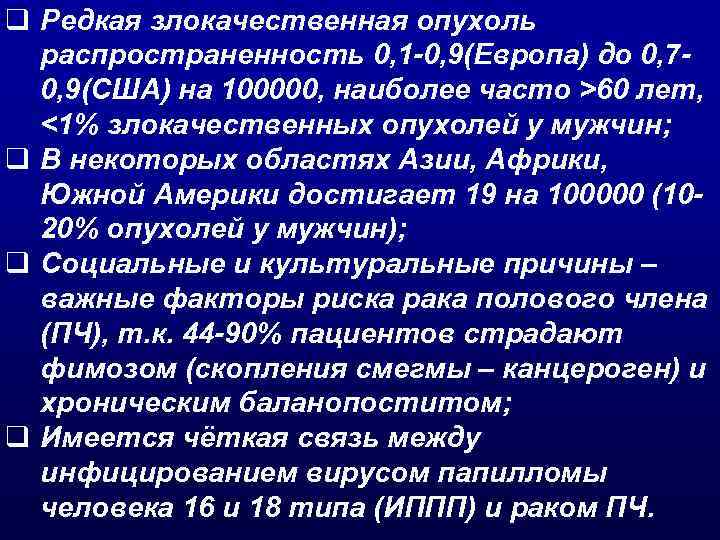

q Редкая злокачественная опухоль распространенность 0, 1 -0, 9(Европа) до 0, 70, 9(США) на 100000, наиболее часто >60 лет, <1% злокачественных опухолей у мужчин; q В некоторых областях Азии, Африки, Южной Америки достигает 19 на 100000 (1020% опухолей у мужчин); q Социальные и культуральные причины – важные факторы риска рака полового члена (ПЧ), т. к. 44 -90% пациентов страдают фимозом (скопления смегмы – канцероген) и хроническим баланопоститом; q Имеется чёткая связь между инфицированием вирусом папилломы человека 16 и 18 типа (ИППП) и раком ПЧ.

q Редкая злокачественная опухоль распространенность 0, 1 -0, 9(Европа) до 0, 70, 9(США) на 100000, наиболее часто >60 лет, <1% злокачественных опухолей у мужчин; q В некоторых областях Азии, Африки, Южной Америки достигает 19 на 100000 (1020% опухолей у мужчин); q Социальные и культуральные причины – важные факторы риска рака полового члена (ПЧ), т. к. 44 -90% пациентов страдают фимозом (скопления смегмы – канцероген) и хроническим баланопоститом; q Имеется чёткая связь между инфицированием вирусом папилломы человека 16 и 18 типа (ИППП) и раком ПЧ.